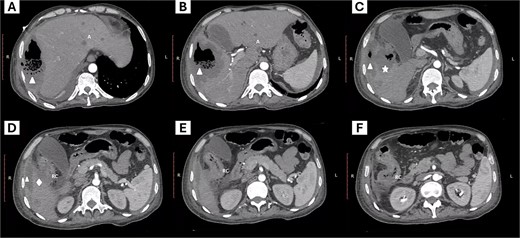

We present the case of a 44-year-old man with no history of chronic diseases who was admitted to the emergency department with a one-week history of diffuse abdominal pain, predominantly in the right hypochondrium, and fever. Physical examination showed tachycardia (144 beats per minute), blood pressure 120/86 mm/Hg, generalized abdominal pain on palpation without peritoneal signs, and a palpable mass in the right upper quadrant. Laboratory tests showed leukocytosis (17 000/mm3), neutrophilia (82%), severe anemia (hemoglobin levels of 6.8 g/dl), platelet count 148 000/mm3, serum creatinine 0.7 mg/dl, moderate hyponatremia (128 mmol/L), and hypoalbuminemia (1.6 g/dl). A contrasted abdominal computed tomography was requested as part of his approach, showing thickening of the right colon wall and perforation of the colon wall at the level of the hepatic flexure with communication to a subphrenic abscess with segmental destruction of the right hepatic lobe parenchyma and diffusely distributed hepatic abscesses (Fig. 1).

Abdominal computed tomography. The images from left to right show the cephalocaudal sequence of the tomography. (A–C) show a subphrenic abscess (triangle symbol) communicating with a hepatic abscess with compromise of the hepatic parenchyma (star symbol), and the site of colon rupture with communication to the abscess (rhombus symbol). Additionally, peripheral hepatic abscesses are visible (letter A). Images D–E show the site of communication of the colon with the abscessed region and the inflammatory process of the right colon (letters RC).